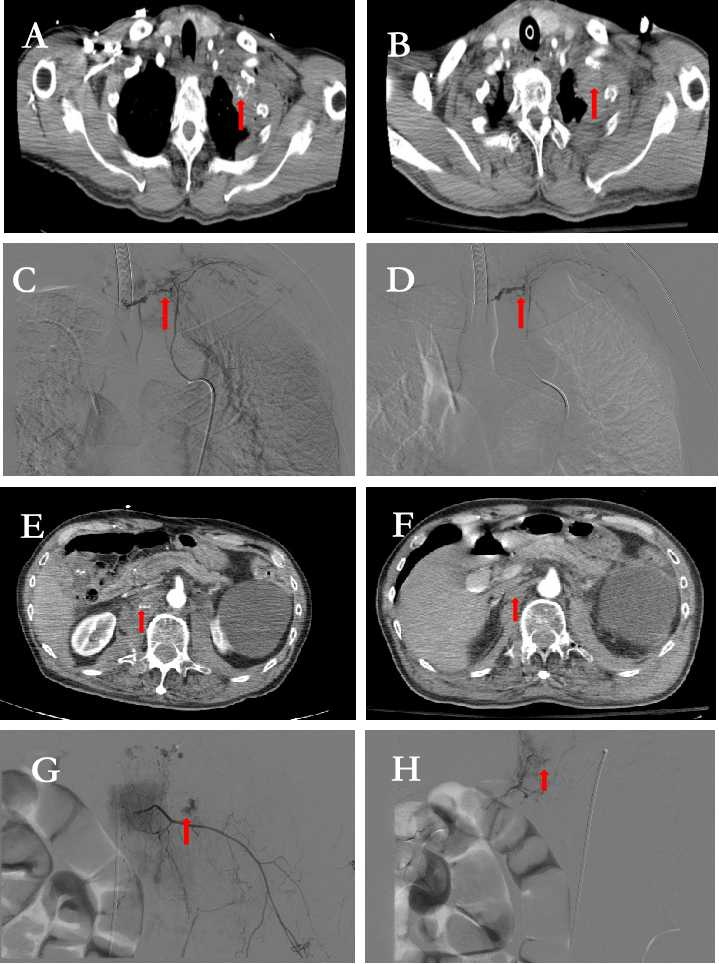

入院后血压持续下降、并出现嗜睡,予以补液、去甲肾上腺素、输悬浮红细胞4 U等治疗的同时,快速行急诊计算机断层扫描(computed tomography, CT)检查提示:蛛网膜下腔出血;左侧多发肋骨骨折,胸壁软组织内活动性造影剂溢出;双侧液气胸;椎前血肿形成,造影剂溢出(图 1A,图 1E);胸椎体骨折(T2、T12),腰椎(L1~L3)骨折、右侧髋臼骨折和耻骨下支骨折。诊断:(1)创伤性蛛网膜下腔出血;(2)肋骨骨折(左侧第1、2、12肋),肋间动脉破裂出血(左第1肋间动脉),血气胸(双侧);(3)胸椎骨折(T2、T12),截瘫;(4)腰椎骨折(L1~L3),椎前血肿:腰动脉损伤?(5)骨盆骨折。急诊行介入手术,经右侧股动脉穿刺插管成功后造影示右侧L1、双侧L2腰动脉、左第1肋间动脉造造影剂外溢,行上述部位动脉栓塞术(图 1C、图 1G),提示造影剂外溢消失(图 1D、图 1H),手术结束转入ICU进一步治疗。术后复查CT:左侧胸壁内造影剂明显减少;L1~L2水平两侧腰大肌未见造影剂。患者病情逐步稳定好转,术后12 d转出ICU进入普通病房,第18天出院,随访至今恢复良好。

| A:增强CT显示左侧胸壁软组织内造影剂溢出(红色箭头);B:术后增强CT显示左侧胸壁软组织内未见造影剂外溢;C:造影显示左侧第一肋间动脉远端截断、造影剂外溢(红色箭头);D:第一肋间动脉血管栓塞术后(箭头),未见造影剂外溢;E:椎前血肿形成,造影剂溢出;F:椎前血肿形成,未见造影剂外溢;G:右L1+双侧L2动脉血管栓塞术后(箭头),未见造影剂外溢;H:术后增强CT显示L1动脉、双侧L2腰动脉未见造影剂外溢 图 1 患者术前术后增强CT及DSA影像 |